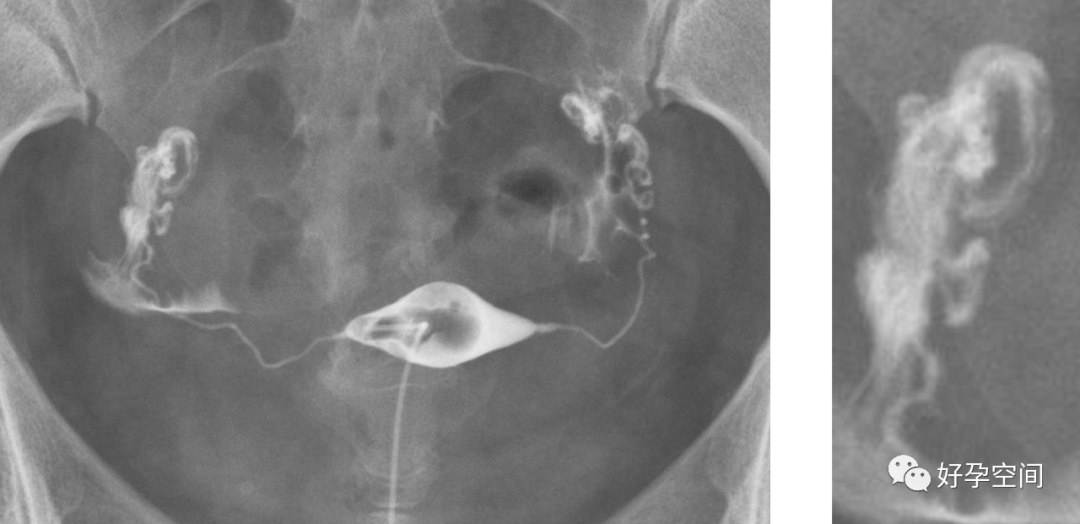

7、输卵管功能评估

输卵管粘膜正常收缩

输卵管粘膜正常舒张

输卵管积水,输卵管柔软自然,粘膜清晰

输卵管积水,串珠样改变,功能丧失

输卵管积水,输卵管像风干的腊肠,粘膜近消失,功能丧失

输卵管阻塞,走行僵硬

,功能丧失